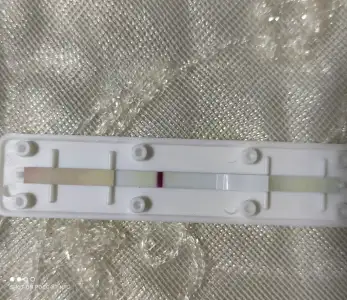

Durdukça belirginlesti ama ilk 2 dakika da çıktı hemen ben gözle görüyorumİkinci de var gibi sanki

Canım bak burda daha net. Eşim bebetime almış ama içinden farklı kaset test çıktı, bebetime'nin iki çeşit kaset testi var. Diğeri hüsrana uğratmıştı

Gördüm gördüm bende çiçeğim yarin hemen kan ver benceDurdukça belirginlesti ama ilk 2 dakika da çıktı hemen ben gözle görüyorum

hanımlar yapar yapmaz çıktı ben gözle cok net toz pembe bir sekilde görebiliyorum ama fotografa bu kadar yansıtabildim çünkü herkes uyuyor perdeleri açıp gün ışığında cekemedim onu da cekicem

yumurtlamadan sonra 11. Gün bugün, bu sefer olmus olsun

Erken gebelik testi alıp yarın ilk idrarla yapsana canım daha koyu cikar çizgiKuzu bebetime ama iki çeşidi var digerinden degil builk iki dakka hemen çıktı çok silik ama yumurtlamamin 11. Günü

Var var attığın tüm fotoğraflarda gördüm kuzu gözün aydınKuzu bebetime ama iki çeşidi var digerinden degil builk iki dakka hemen çıktı çok silik ama yumurtlamamin 11. Günü